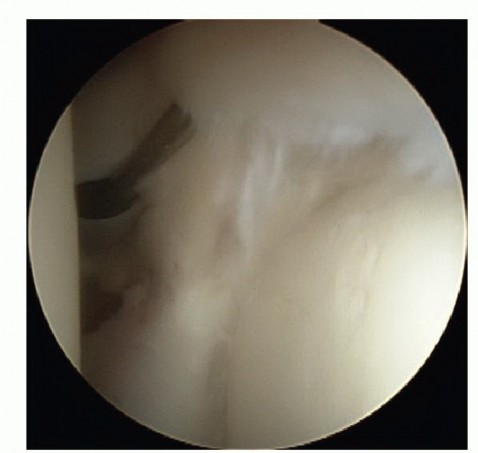

DEFINITION Osteochondritis dissecans (OCD) is described as a focal, idiopathic alteration of subchondral bone…